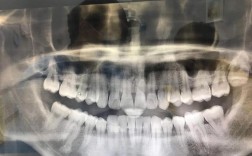

矫正牙齿前,医生通常会建议进行一系列影像学检查,这些片子是制定精准治疗方案、规避风险的重要依据,不同类型的片子从不同角度展示口腔及颌面部结构,帮助医生全面评估牙齿、牙根、牙槽骨、颌骨关系及面部软组织情况,从而设计出个性化的矫正方案,全景片(...